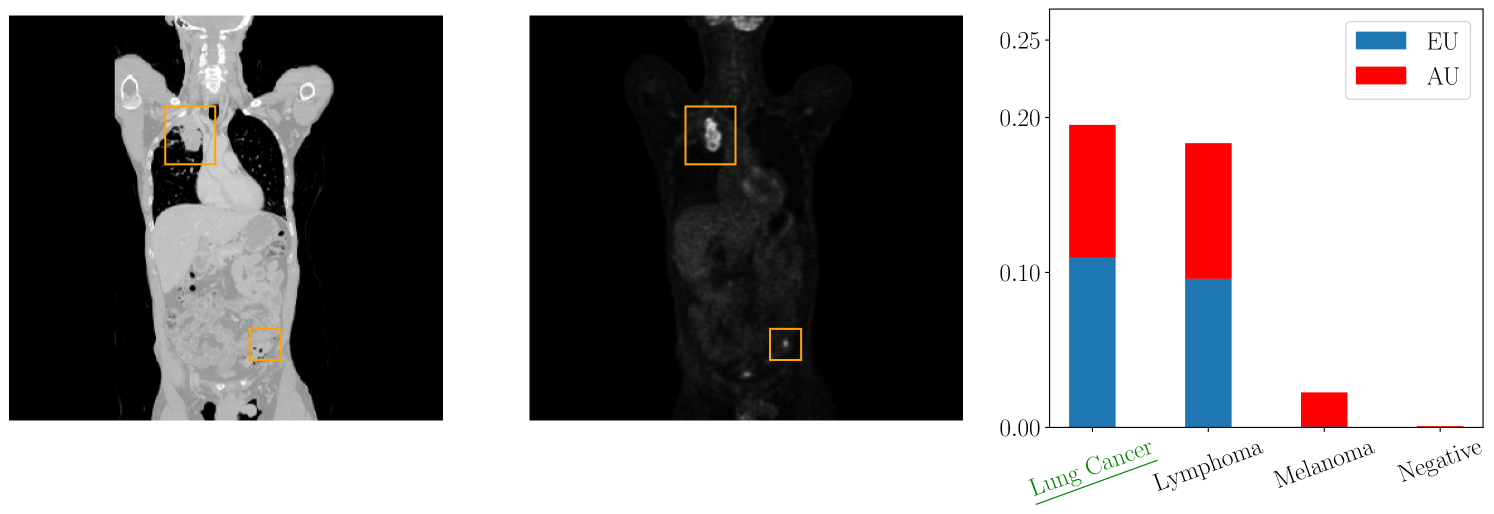

For the evaluation in the medical domain, we use a data set of Positron Emission Tomography/Computed Tomography (PET/CT) images which comprises 501 full-body scans from patients with malignant lymphoma, melanoma, and lung cancer, as well as 513 scans from individuals without malignant lesions (negative controls) [Gatidis et al., 2022]. Each scan is annotated with a tumor segmentation performed by a medical expert. We extract from each 3D CT and PET volume multiple 2D images which are used to train a deep neural network ensemble and evaluate the label-wise uncertainty quantification.

Figure 2 depicts a qualitative example of a 2D PET/CT image from the data set with the corresponding label-wise uncertainties from our evaluation. We observe low aleatoric uncertainty and negligible epistemic uncertainty for the melanoma class. This implies that the approximation of the aleatoric uncertainty is reliable. On the contrary, the classes lung cancer and lymphoma are associated with high aleatoric and high epistemic uncertainty, suggesting that the prediction with respect to these classes may not be accurate. This observation is plausible from a medical perspective as we observe multiple tumors in the image which are not limited to the lung area and thus might indicate a different tumor class as well. In this instance, we could request a medical expert to annotate additional data for the classes lung cancer and lymphoma, thereby diminishing the epistemic uncertainty associated with these classes. Here, a global measure of uncertainty would only give epistemic uncertainty with respect to all classes, meaning a doctor would have to annotate data for all classes.

Having a more detailed understanding of the label-wise uncertainties is crucial for the decision-making in medical applications supporting a given diagnosis. Moreover, it allocates resources to the relevant classes and saves valuable examination time and costs.

Figure 4 presents additional medical images with the highest total, aleatoric, and epistemic uncertainties. Similarly, Figure 5 showcases images with the highest total, aleatoric, and epistemic uncertainties for the MNIST data set.